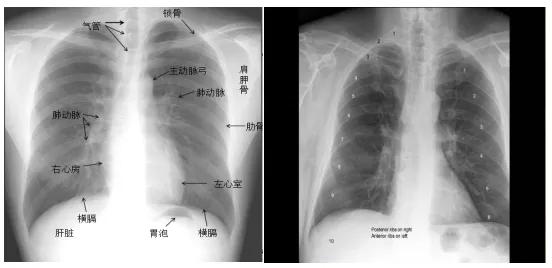

超详细胸片教学 不信你还学不会!

"0"基础小白必备宝典:认识肺部影像结构

肺部胸片

胸片图片

胸片正常图片

正常胸片图片图解

肺部正常胸片影像图片

正常肺部胸片

正常人胸片图片

正常人的肺部胸片图

正常胸片影像图片